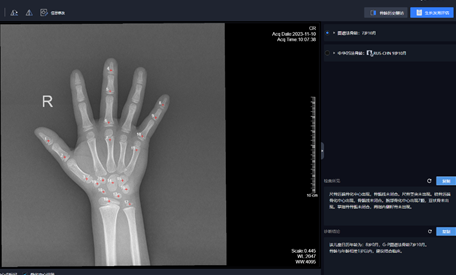

我科现采用人工智能系统智能识别骨骺、分级以及骨龄计算,大大提高骨龄评估的工作效率,提高了诊断的准确性。

人工智能在骨龄评估中的应用